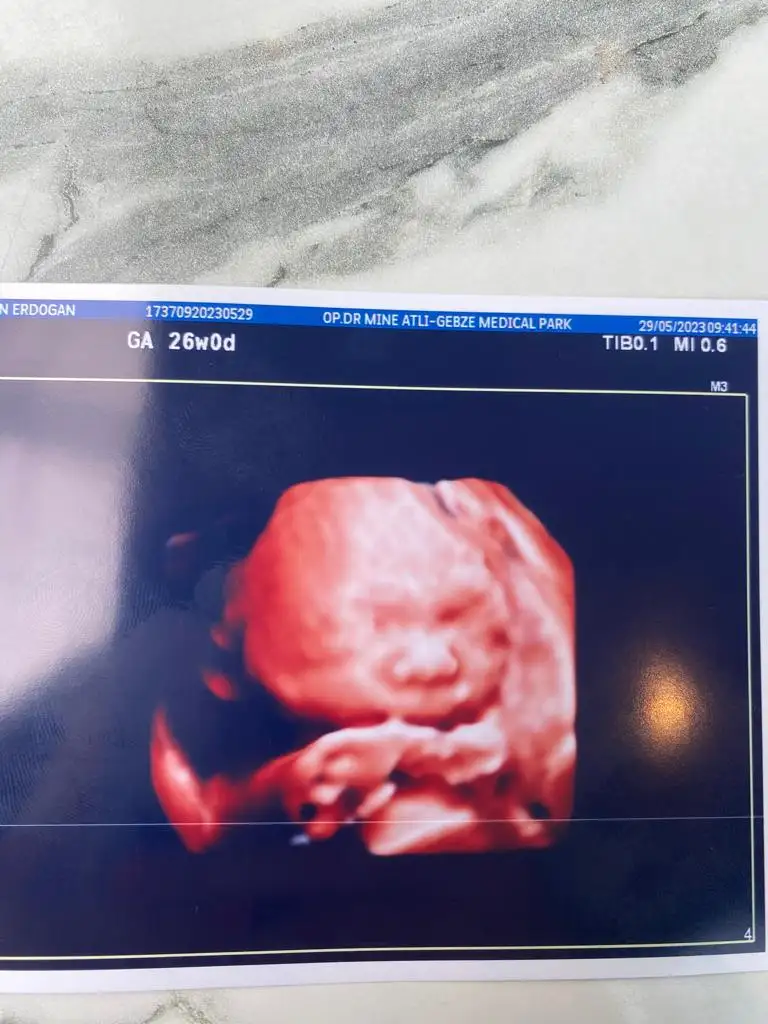

En son ayın 1 inde gitmiştim doktora 25+5 im bende cumartesi doktor kontrolüm var bakalım bebiş kilo almış mı uzamış mı göreceğizKızlar bugün kontrolümüz var 24+3 olduk. Çok az kaldı farkında mısınız? Geçen gün arkadaşım doğum yaptı. Şimdi daha hızlı geçecek günler dedi. Siz kaç hafta oldunuz bebişler kaç gram olmuşlar ? Ayy inanamıyorum hala karnımda bebek üretiyorum ya

Oyş az kalmış ya yakında bir kilo olacak minnoşBenim şu an 25+1 ancak son kontrole 24+5te gitmiştim kilosu 750 gr boyu da 32-33 cm arası demişti doktorumuz.

Maşallah annesi doğsunda ye sen onun yanaklarını yaaKizlar 890 gr 32 cm olmus tombik yanaklı kizimseker yüklemesi de yapıldı bekliyorum sonucunu

Yiyceeemm ben bu tombik yanağıKizlar 890 gr 32 cm olmus tombik yanaklı kizimseker yüklemesi de yapıldı bekliyorum sonucunu